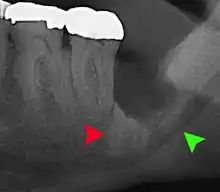

Long-term complications can include periodontal complications such as bone loss on the second molar following wisdom teeth removal. Bone loss as a complication after wisdom teeth removal is uncommon in the young but present in 43% of those of 25 years of age or older.[22] Injury to the inferior alveolar nerve resulting in numbness or partial numbness of the lower lip and chin has reported rates that vary widely from 0.04% to 5%.[22] The largest study is from a survey of 535 oral and maxillofacial surgeons in California, where a rate of 1:2,500 was reported.[25]

Coronectomy

Coronectomy is a procedure where the crown of the impacted wisdom tooth is removed, but the roots are intentionally left in place. It is indicated when there is no disease of the dental pulp or infection around the crown of the tooth, and there is a high risk of inferior alveolar nerve injury.[31]